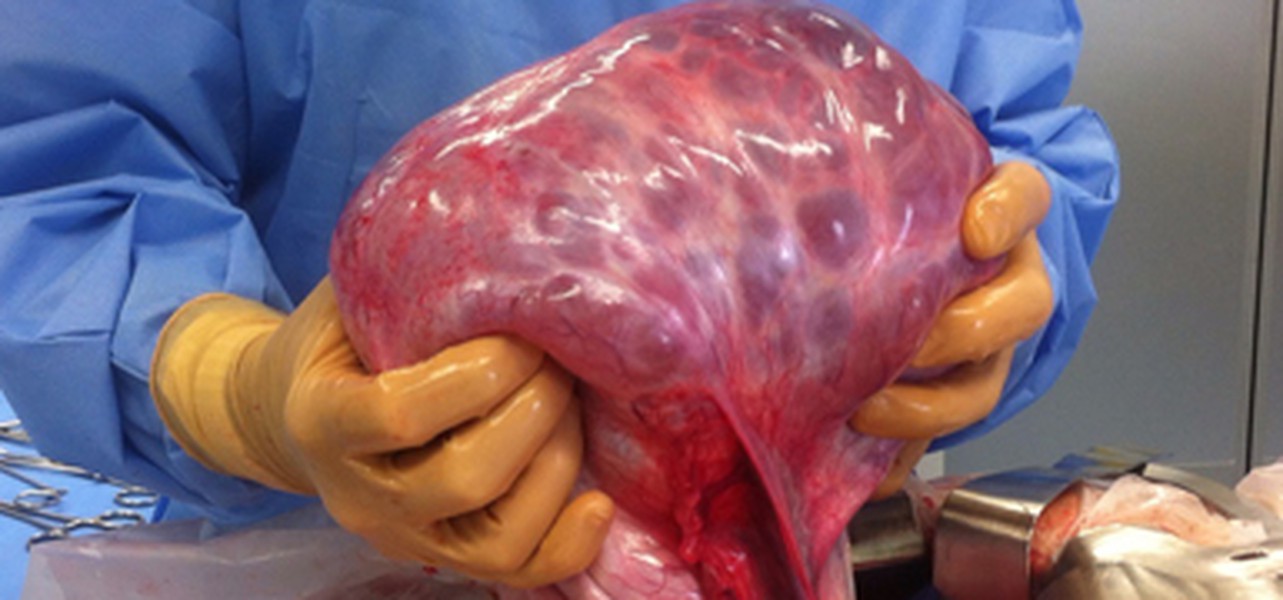

Figure 1 Hémangiome infantileImage Volumineuse tumeur hépatique chez une femme de 50 ans (Wikimedia Commons/ Haitham Alfalah) L'incidence du cancer primitif du foie (tumeurs des voies biliaires incluses) augmente régulièrement dans le monde Il est au 3e rang des décès par cancer après ceux duLe carcinome basocellulaire (CBC) est la forme la plus courante de cancer de la peau et la forme la plus fréquente de tous les cancers Rien qu'aux ÉtatsUnis, plus de 4 millions de cas sont diagnostiqués chaque année Les CBC résultent d'une croissance anormale et incontrôlée des cellules basales

Apr 01, 12 · Download Download fullsize image;Dec 01, 00 · Actuellement, les critères de diagnostic différentiel entre les tumeurs trophoblastiques du site d'implantation placentaire bénignes et malignes ne sont pas entièrement établis Download Download fullsize image;Figure 1 Macroscopie d'hystérectomies pour tumeurs myxoïdes de l'utérus Le nodule stromal fibromyxoïde (A) et le léiomyome myxoïde (B) sont des tumeurs bien limitées, intramurales, avec un aspect gélatineux, blancjaunâtre